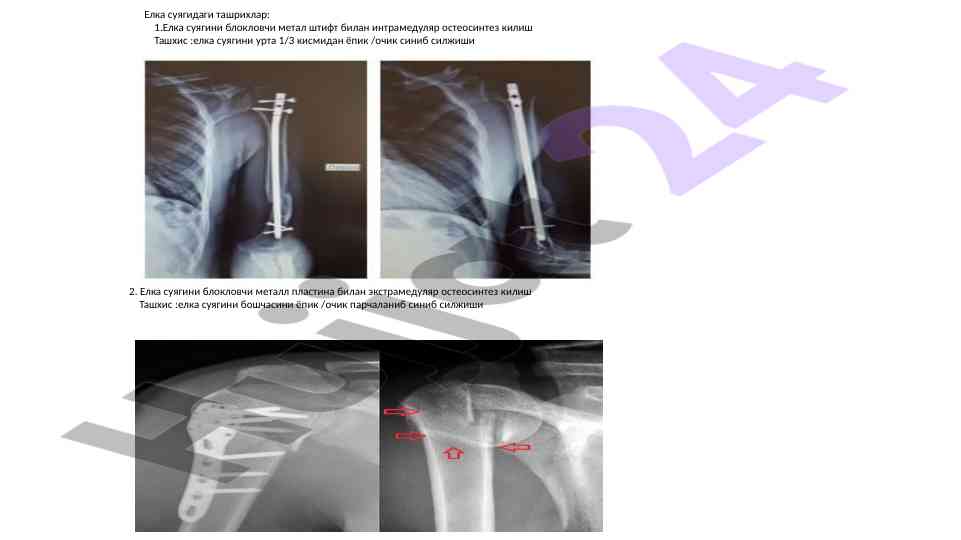

Ushbu ilmiy maqola zamonaviy travmatologiya asoslari, jarohatlarni diagnostika qilish va davolash usullarini takomillashtirish haqida ma'lumotlar taqdim etadi.